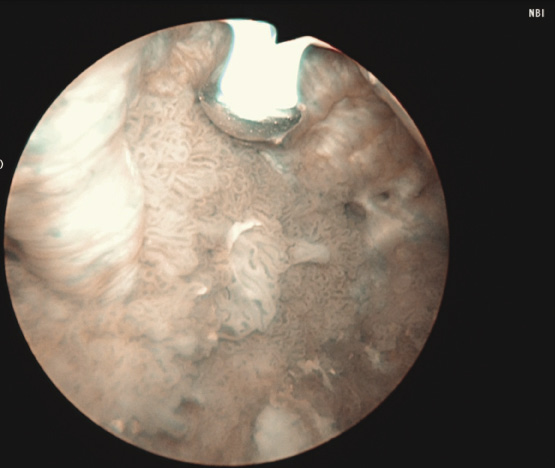

3) Complete cystoscopy is then performed in the standard fashion using WLI to re-identify the primary tumor as well as to assess for tumor multifocality, Figure 1a. This assessment is sometimes more easily done in the operating room with the patient under anesthesia. Once cystoscopy is completed with WLI, we then switch to NBI by pressing the button on the camera cord. A repeat thorough cystoscopy is then done, specifically looking for areas of hypervascularity in the mucosa, Figure 1b. These areas most likely represent occult bladder lesions. These occult lesions will be biopsied. Also, we use NBI to assess the peri-tumor vascularity to try and determine the demarcation between hyper vascular tissue and normal appearing mucosa and sub-mucosa, Figure 2. Our goal is to resect/vaporize all hypervascular tissue to a margin of normal appearing bladder mucosa and sub-mucosa.

DrCanter_Fig2_CMYK.eps

Figure 2. Adjunctive use of Narrow Band Imaging during bladder tumor resection using the Button Bipolar electrode. Narrow Band Imaging helps to delineate vascularity associated with tumor and vascularity of normal surrounding urothelium.